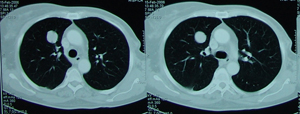

Εικόνα 3

Αξονική τομογραφία θώρακος που δείχνει μάζα εκ μαλακών μορίων στο πρόσθιο τμήμα του δεξιού άνω λοβού. Η μάζα έχει ομοιογενή σύσταση με ομαλά όρια.